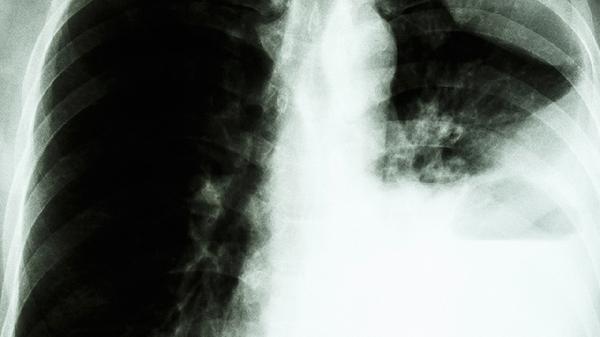

特发性肺间质纤维化的症状及治疗

特发性肺间质纤维化主要表现为进行性呼吸困难、干咳和杵状指,可通过抗纤维化药物、氧疗及肺康复等方式治疗。该病可能与吸烟、环境暴露、胃食管反流等因素有关,晚期可能出现肺动脉高压和呼吸衰竭。